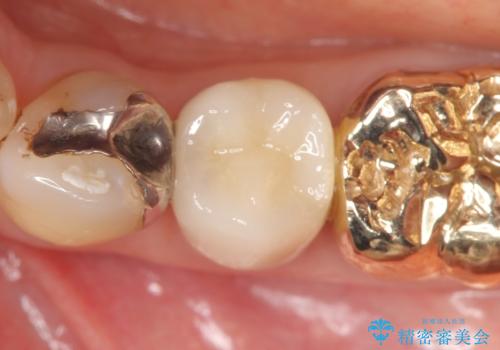

再根管治療終了後、オールセラミッククラウンによる補綴を行いました。

今回用いたオールセラミッククラウンはジルコニアフレームという白い素材の上にセラミックを盛っているため、審美性が非常に高いのが特徴です。

また、ジルコニアは人工ダイヤモンドの材料にも使われているほど高い強度を持っており、そのためオールセラミッククラウンは審美性だけでなく、奥歯やブリッジの補綴も可能とするクラウンです。